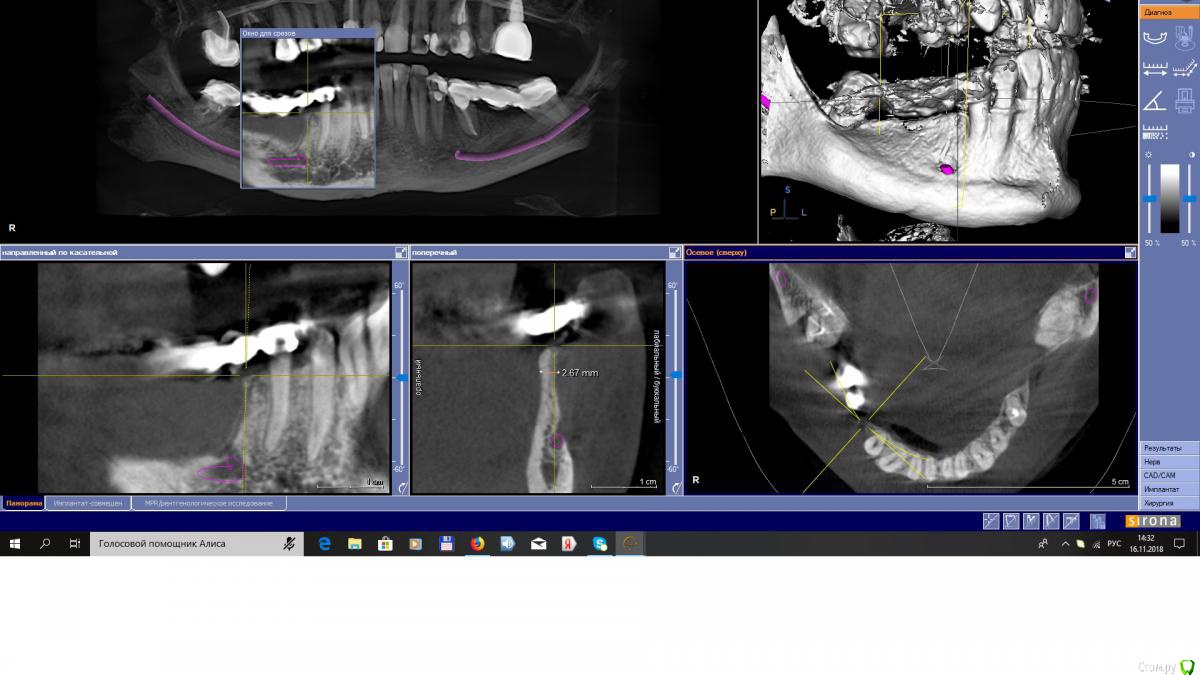

EEcho Опубликовано 16 ноября, 2018 Поделиться Опубликовано 16 ноября, 2018 Коллеги, добрый день!Ваши варианты при такой атрофии. Ссылка на комментарий

EEcho Опубликовано 22 ноября, 2018 Автор Поделиться Опубликовано 22 ноября, 2018 Это понятно, что можно любую методику кроме расщепления и моноблоков, но как в этом случае обойти ментальное отверстие с выходом сосудисто-нервного пучка почти вертикально? Резать мембрану обходя отверстие и бить кнопки вокруг, то есть сосиську по Урбану, с эволюшкой.? или делать каркас из мини пластин.? полужестким каркасом отверстие будет не обойти.( возможно графт будет через него высыпаться или врастет через него соединительная ткань)? Ссылка на комментарий